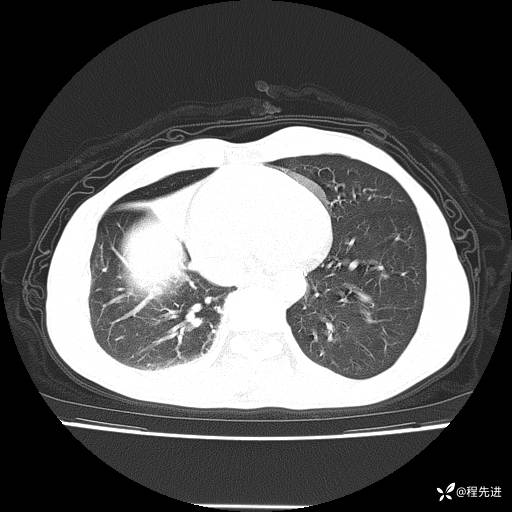

患者性别:男

患者年龄:49岁

主诉:咳嗽、胸痛1周

简要病史:1周前受凉感冒后开始出现咳嗽症状,阵发性连声咳,痰多,黄白痰,不易咳出,伴胸痛、气紧、胸闷,右侧为主,活动用力、呼吸时胸痛明显,曾在当地诊所贴敷膏药仍疼痛

体格检查:T:36.3 ℃ P:80 次/分 R:20 次/分 BP:120/88 mmHg,指脉氧饱和度97%,意识清晰,呼吸平稳,右侧第二、三肋骨压痛,可见膏药贴敷,皮肤无异常,双肺呼吸音粗,未闻及干湿性啰音。心率80次/分,节律整齐,无杂音。腹平软,全腹无压痛无反跳痛

临床诊断:社区获得性肺炎

CT平扫: